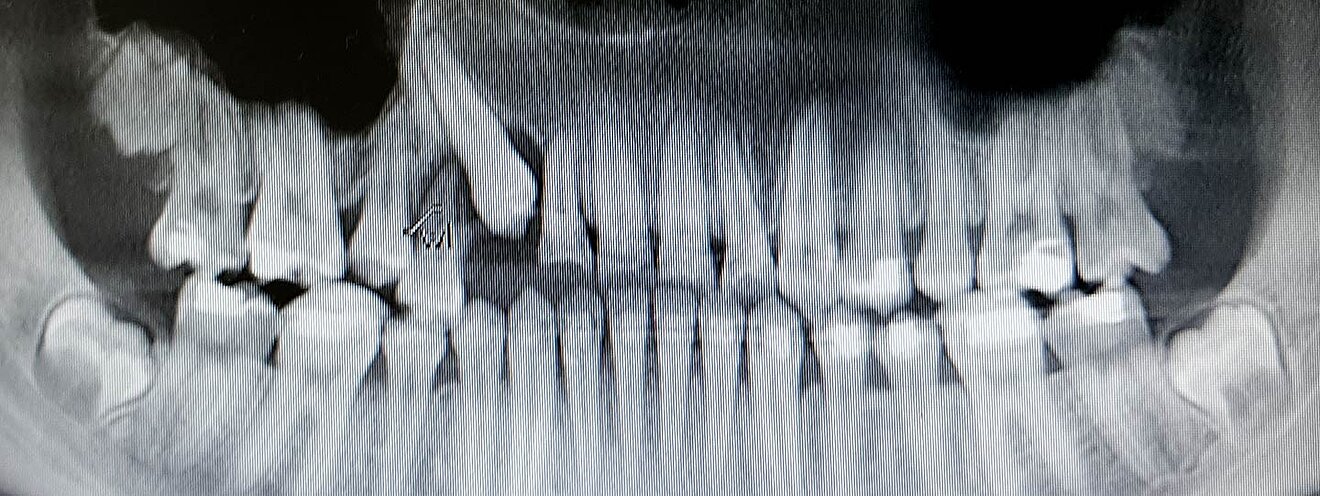

Verlagerte Zähne sind Zähne, die nicht an ihrer regulären Position im Kiefer durchbrechen, sondern an einer ungewöhnlichen Stelle verbleiben oder sogar im Kieferknochen eingeschlossen bleiben. Eine frühzeitige Diagnose und Behandlung ist wichtig, um Komplikationen wie Zahnfehlstellungen, Schmerzen oder Schäden an benachbarten Zähnen zu vermeiden.

Vor der Behandlung wird der verlagerte Zahn durch Röntgenbilder oder dreidimensionale Aufnahmen (DVT) genau lokalisiert.